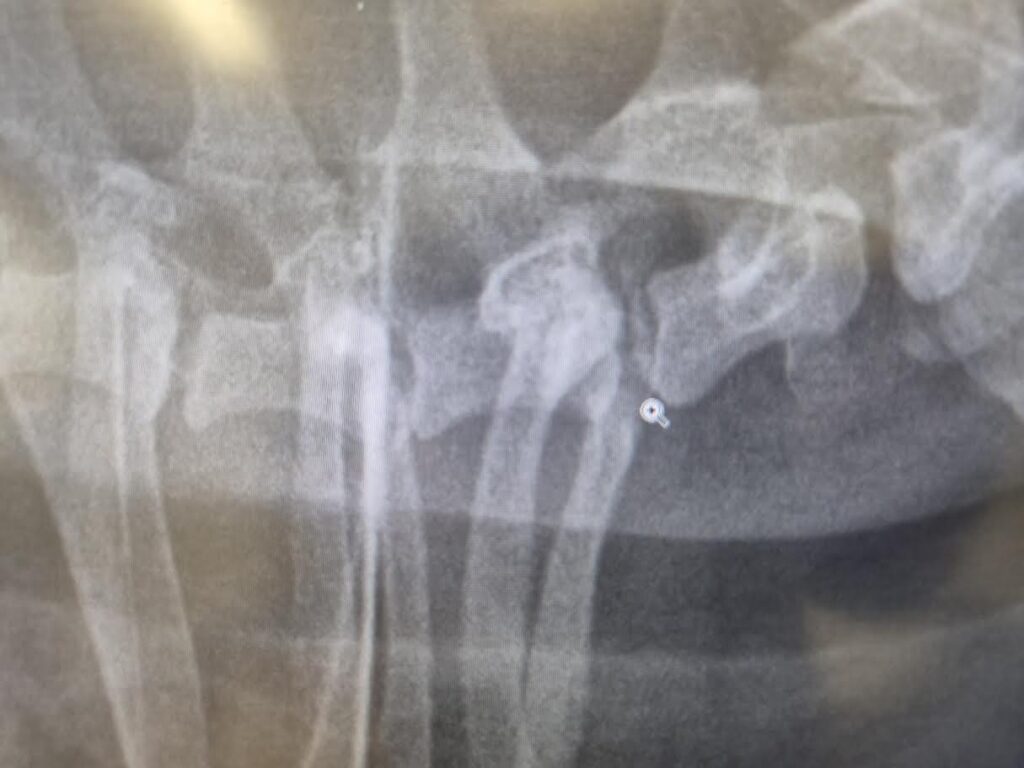

Luna alkoi piippaamaan mm. sen hyppäessä sohvalta alas ja kun sitä nostetaan syliin, joten pikapikaa KokkoVetille röntgeniin. Tuloksena kalkkeuma viimeisen niskanikaman ja ensimmäisen rintanikaman välissä. Ei spondyloosia. Parantumaton vika, mutta kokeillaan särkylääkkeitä näin alkuun kuurina josko saataisiin edes vähän enemmän aikaa yhdessä.